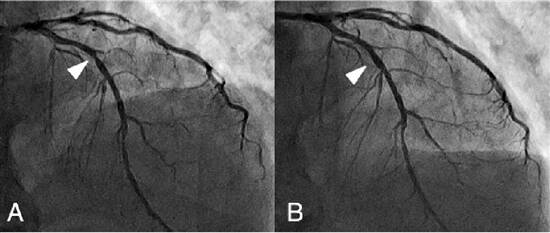

冠状动脉支架植入前后对比 |